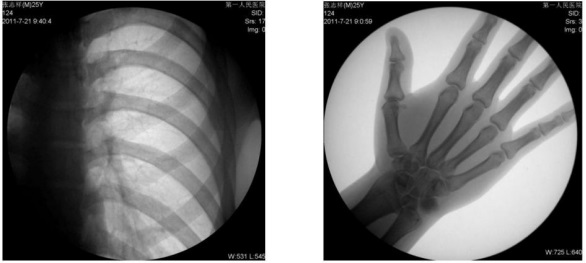

1、数字化透视:适用于全身各部位透视(如胸透、腹透等)。

动态采集速度≥25 帧/秒,主要应用于临床各科室,尤其是体检科、内科、外科、骨科、创伤科、急诊科等。

1) 胸部检查:能实现全胸透视动态观察,对于需要在透视下动态观察的病变,如肺部肿瘤、气管异物等可进行实时点片。胸部透视是体检中的常规检查项目,临床意义在于检查有无肺癌, 特别是早期肺癌。使用胃肠机可通过胸部透视双肺,纵膈有无病变,以确定病变部位的部位、大小、密度,与周边组织关系,常见的疾病,如肺炎、肺结核等。胃肠机可以从各种角度动态详细观察肺、心脏或其他胸部的病变,对病变的情况可以有个比较全面地了解。